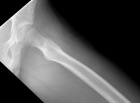

J.G. - 14 year old male c/o left posterior thigh mass for eight months. His mother noticed the mass, but no ecchymosis, after he fell while running hurdles. He complains of pain only when running long distances, and with prolonged pressure. It has decreased in size only minimally. No F/C.